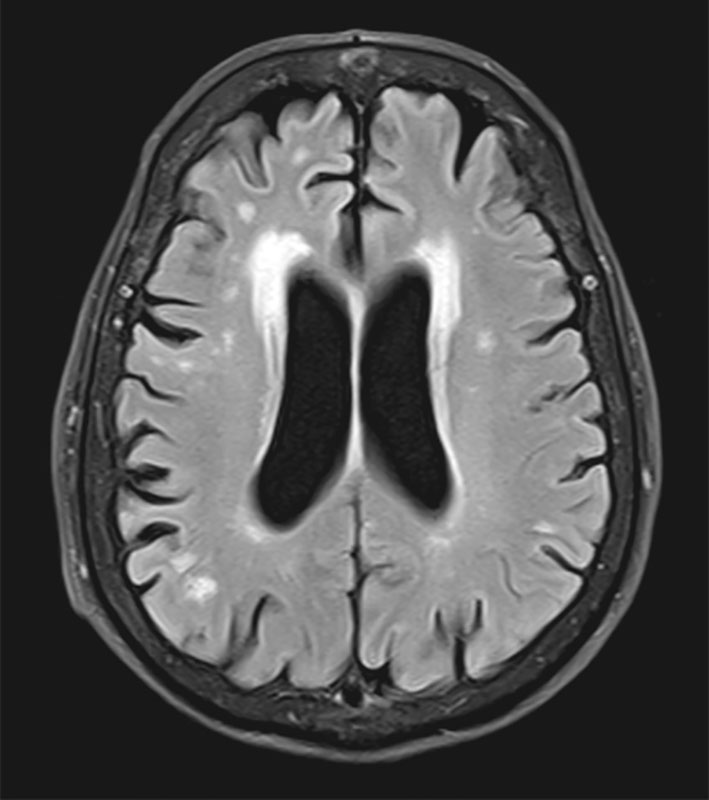

Хроническая ишемия головного мозга и лейкоареоз: симптомы и лечение